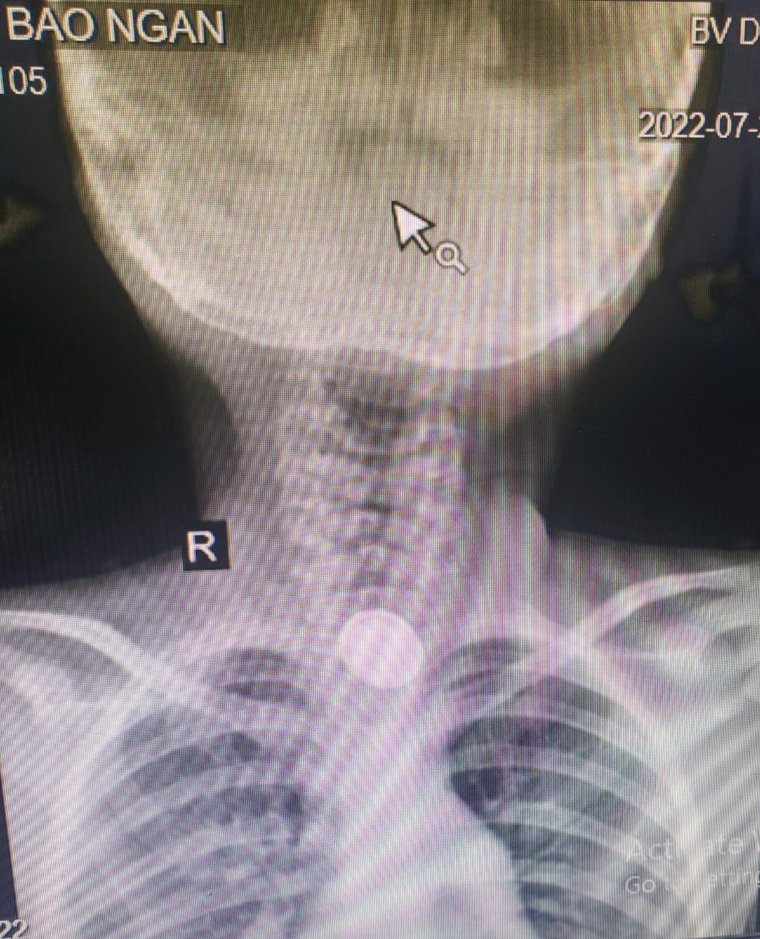

Hình ảnh dị vật pin cúc trên phim chụp X quang cổ

Qua hỏi bệnh, thăm khám và kinh nghiệm lâm sàng, các bác sỹ khoa Tai Mũi Họng đã xác định dị vật trẻ nuốt phải là Pin cúc, là một cấp cứu khẩn cấp. Trẻ nhanh chóng được chuyển lên khoa gây mê để tiến hành lấy dị vật. Bằng kinh nghiệm, sự nỗ lực của ê kíp gây mê và phẫu thuật, với trang thiết bị nội soi hiện đại, các bác sĩ khoa Tai Mũi Họng đã tiến hành nội soi thực quản ống cứng lấy ra được dị vật là viên pin cúc áo đường kính 2cm, phủ dịch rỉ nâu đen, tại thực quản vị trí dị vật nằm đã có hiện tượng viêm hoại tử niêm mạc. Sau lấy dị vật bệnh nhân được điều trị và được nội soi tiêu hóa ống mềm ngày thứ 2 đánh giá kết quả, tổn thương tại vị trí dị vật nằm còn rất nặng nề.